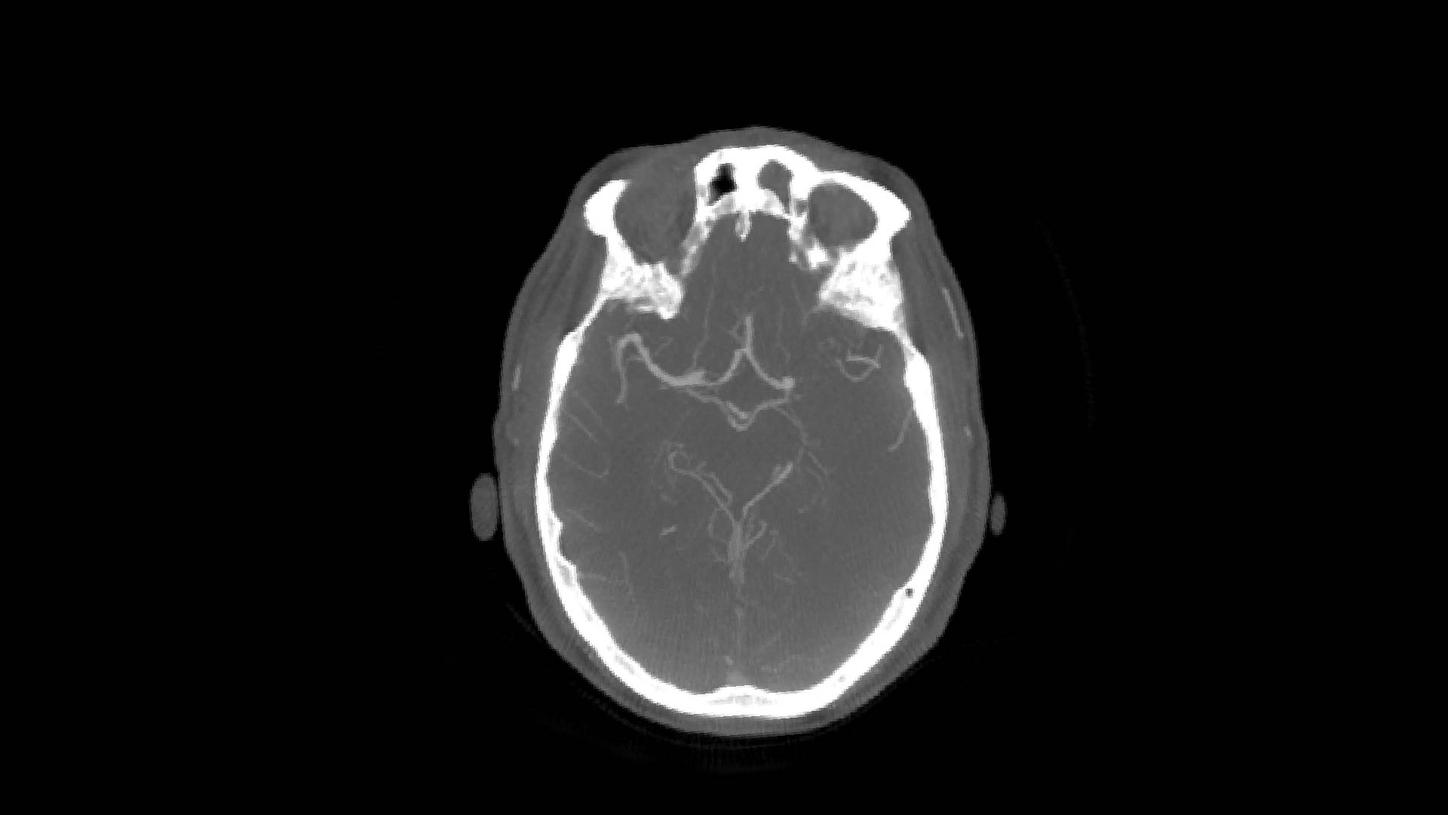

Paciente de 56 años con un accidente cerebrovascular despertado, presentando hemiparesia en el lado derecho y disartria, NIHSS 11.

Oclusión de la M1 en el lado izquierdo debido a una estenosis aterosclerótica intracraneal subyacente.

Primera ejecución de syngo DynaCT Multiphase antes de la trombectomía